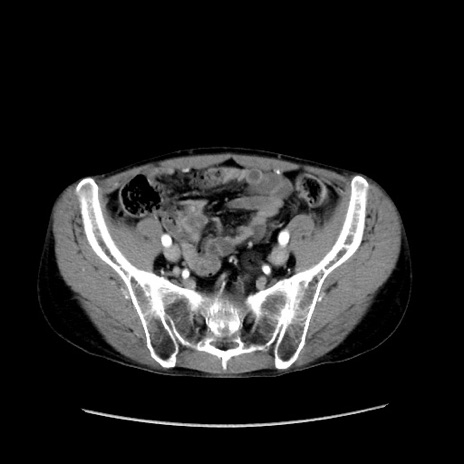

症例37(横断像)

【症例】40歳代 男性

【主訴】腹痛

【現病歴】4時間ほど前に電車に乗車中に臍部上より腹痛出現。徐々に増悪し起立困難となり、救急外来受診。生ものは数日食べていない。今朝お雑煮を食べた。

【身体所見】BT 36.8℃、BP 117/84mmHg、HR 91/min、SpO2 97%、苦悶様、腹部:臍上部広範囲圧痛あり、反跳痛±

【データ】WBC 8100、CRP 0.03